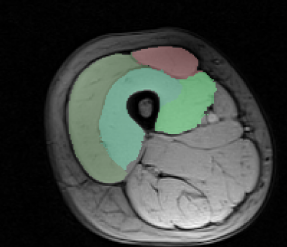

Dataset. The dataset consists of 30 MRI volumes of the thigh region of dimensions . The various segments correspond to 4 different muscle groups together with the background class. We randomly split the dataset into 80% for training and 20% for testing. In order to reduce the training time for both our method and the baselines, we divide each volume into volumes of dimension .

Results. Fig. 1 shows the test loss for three different methods: (i) the initial hand-tuned parameters ; (ii) the baseline structured SVM with distance transforms; and (iii) our proposed approach using latent SVM. As can be seen from Fig. 1, latent SVM provides significantly better results than the baselines—even when using the distance transform. For the 4 x 5 hyperparameter settings that we report (that is, four different values of and 5 different values of ), latent SVM is significantly better than SVM in 15 cases, and significantly worse in only 2 cases. Note that latent SVM provides the best results for very small values of , which indicates that the upper bound on the empirical risk in tight. As expected, for sufficiently large values of , all the methods provide similar results. For the best settings of the corresponding hyperparameters, the percentage of incorrectly labeled voxels as follows: (i) for , ; (ii) for structured SVM, ; and (iii) for latent SVM, . Fig. 2 shows some example segmentations for the various methods.